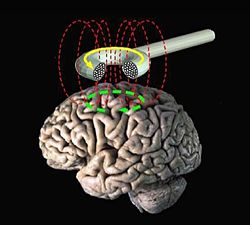

הגירוי המגנטי המוחי הוא שיטה, לא פולשנית, לגרייה (neurostimulation) ואפנון (neuromodulation) של הפעילות המוחית. באמצעותה ניתן לגרום לפוטנציאל פעולה ואף לשינויים נוירופלסטיים (neuroplasticity) באזור מוגדר במוח. עיקר השימוש הקליני בגרייה מגנטית מוחית מבוסס על השריית שינויים נוירופלסטיים, קרי עיכוב או עירור הפעילות באזור נבחר במוח, באמצעות שליטה בתדירות ועוצמת הגירוי (נמוכה או גבוהה בהתאמה).

שיטת טיפול לא פולשנית לגרייה של המוח באמצעות טכנולוגיה מגנטית. הטיפול מבוסס על שדות מגנטיים מהסוג בו משתמשים בבדיקת ההדמיה MRI (Magnetic Resonance Imaging), המשרים פעילות חשמלית עדינה במוח, המעוררת פעילות עצבית רצויה באזור הגירוי. הגמ"מ אושר על ידי משרדי הבריאות האמריקאי, האירופאי והישראלי כשיטה בטוחה ויעילה לטיפול בדיכאון.